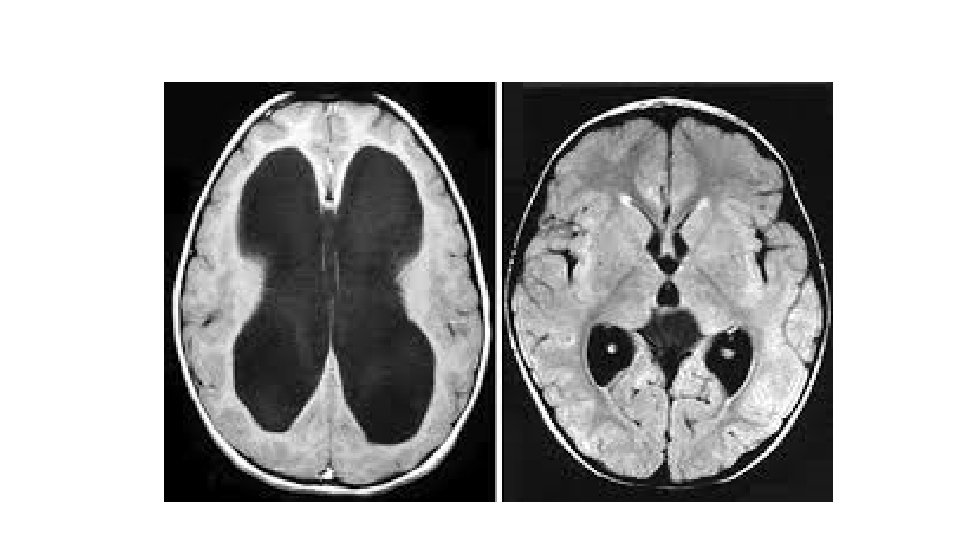

Case II • A 24 year old patient presented to the emergency unit complaining from headache, low grade fever and vomiting for 3 weeks, on examination mild neck stiffness was found. CSF exam showed protein 240 mg/dl, normal sugar and 200 cells: 40% Neutrophils and 60% Lymphocytes. • MRI showed:

• What is the most likely diagnosis? • The patient was treated, discharged home on steroids and anti-TB medications. • Three weeks later: Sever Headache, Vomiting, Weakness and Blurring of vision. • ?